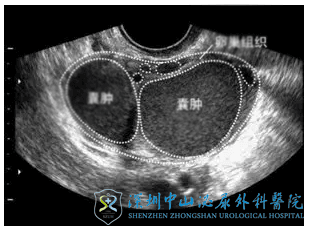

什么是巧克力囊肿?

巧克力囊肿是子宫内膜异位症的一种,病因尚不是很清楚。目前关于病因的学说有:异位种植学说,在位内膜决定论,体腔上皮化生等。目前“内膜异位种植学说”最受推崇,主要说的是,子宫内膜随月经血逆流至盆腔部位种植、生长。若流到盆腔的子宫内膜细胞种植到卵巢上,受到卵巢周期性激素的影响,每月也发生月经样的出血,但血液由于卵巢包膜无法排出,时间长了便形成囊肿。每月的出血长期沉积在囊肿中,质地粘稠,颜色变为巧克力色,便形成了“巧克力囊肿”。